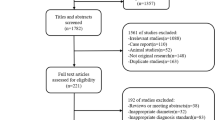

The Az index values for each radiologist and the mean Az index values for the pooled data of the four pairs of imaging modality are shown in Table 1. The composite ROC curves generated from the pooled data of the three independent radiologists are shown in Fig. 1. The diagnostic accuracy (Az values) for nodular HCCs of combined CTAP and CTHA, the combined Gd-DTPA-enhanced dynamic and SPIO-enhanced MR images, the Gd-DTPA-enhanced dynamic MR images, and the SPIO-enhanced MR images for all observers were 0.934, 0.963, 0.878, and 0.869, respectively. The diagnostic accuracy of the combined CTAP and CTHA and the combined Gd-DTPA-enhanced dynamic and SPIO-enhanced MR images was significantly higher than the Gd-DTPA-enhanced dynamic MR images or the SPIO-enhanced MR images (p<0.005). The diagnostic accuracy for nodular HCC was comparable between the combined Gd-DTPA-enhanced dynamic and SPIO-enhanced MR images and the combined CTAP and CTHA (Az=0.963 vs Az=0.934).

Receiver operating characteristic curves for pooled data show the confidence of three radiologists for detection of hepatocellular carcinomas (HCCs) on images obtained with unenhanced and Gd-DTPA-enhanced dynamic MR images (diamonds; Az=0.878), unenhanced and superparamagnetic iron oxide- (SPIO) enhanced MR images (squares; Az=0.869), combined Gd-DTPA-enhanced dynamic and SPIO-enhanced MR images (triangles; Az=0.963), and combined CT during arterial portography and CT during hepatic arteriography (circles; Az=0.934)